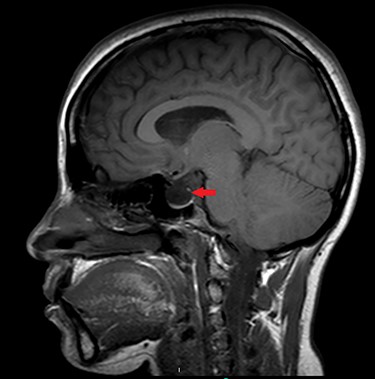

A 36-year-old female patient presented to our emergency department with fever, headache, altered level of consciousness and agitation. Patient provided history of headache and clear watery rhinorrhea from the right side of the nose after nasopharyngeal swab for COVID-19 started four months prior to her presentation. She has a significant past medical history of IIH that was evident by magnetic resonance imaging (MRI) in 2018 with empty Sella Turcica sign (Fig. 1).

Sagittal MRI of brain, T1 weighted image, showing evidence of empty Sella Turcica (arrow).